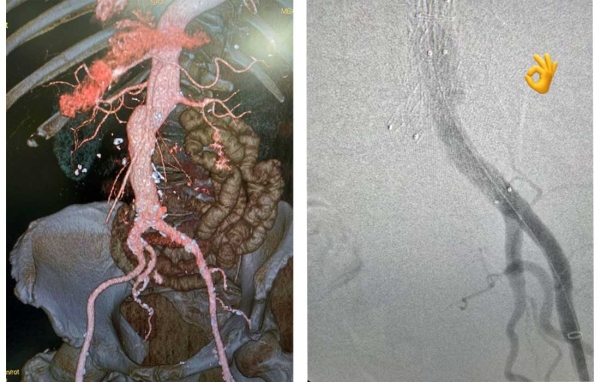

Успешна операция на аневризма на коремна аорта с CO2 за първи път в България

Съдови хирурзи от УМБАЛ „Тракия“ извършиха успешно лечение на полианевризми на коремната аорта с помощта на автоматичния инжектор на контрастни вещества на периферно-съдово ниво Angiodroid. Вместо високомолекулярен йоден контраст, апаратът инжектира в кръвта въглероден диоксид, който също е рентгено контрастен и след 4-5 минути пациента го издишва. Напълно безопасен е и не се налага след операцията кръвта да се пречиства с диализатор от креатинин.

Дигитално-субтракционната ангиография с въглероден диоксид (CO2-DSA) е все по-често използвана техника при ендоваскуларна аортна репарация (EVAR) и фенестрирана (разклонена) EVAR (F/B-EVAR). Тя се използва за предотвратяване на постоперативно влошаване на бъбречната функция (PO-RFW) и при пациенти с алергии към контрасти материи, посочва д-р Павел Атанасов.

Лекарите установяват множество разширения по абдоминалната аорта, подобни на торбички, които тръгват от отделянето на бъбречните артерии и продължават по хълбочните артерии на двата крака, където аневризмите са достигали до над 2 - 3 сантиметра.

„По време на операцията аневризмите на аортния и по илиячния сегмент бяха изолирани, след като успешно изолирахме кръвотока, благодарение на ясните анатомични ориентири, получени от визуализацията с CO2 и устройствата, с които е оборудвана операционната“, посочи д-р Бисеров.